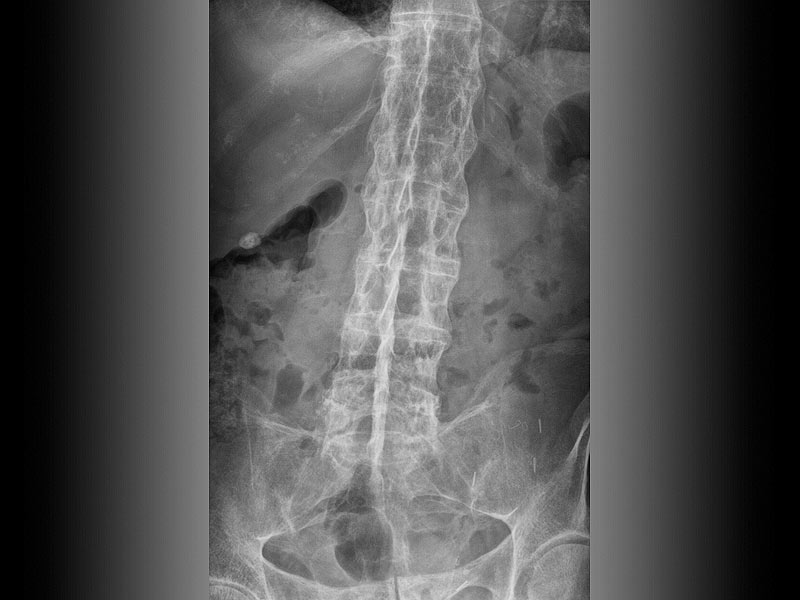

Le délai avant la pose du diagnostic reste un problème prégnant dans la spondylarthrite ankylosante (SPA) en dépit de la publication des critères ASAS (Assessment of Spondylo Arthritis international Society) de 2009 (Rudwaleit M : The development of Assessment of Spondylo Arthritis international Society classification criteria for axial spondyloarthritis [part II] : validation and final selection., Ann Rheum Dis., 2009; 68: 777-784))

Puisque au cours de la SPA, les malades ont des rachialgies chroniques et qu’une uvéite antérieure aiguë (UAA) survient chez 26 % d’entre eux, la coexistence de rachialgies et d’une UAA chez un sujet devrait inciter les médecins généralistes à envisager le diagnostic de SPA.